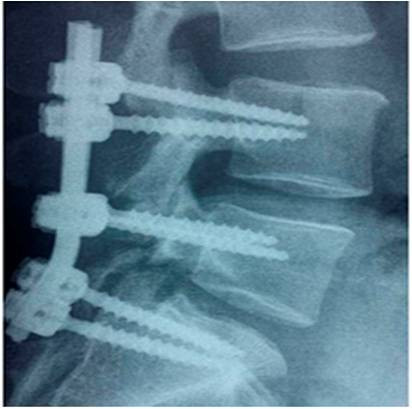

Ողնաշարի գոտկային և կրծքային հատվածների ախտահարումների ժամանակ կատարվում է տրանսպեդիկուլյար ֆիքսացիա. Վիրահատությունը ցուցված է մի քանի մակարդակի ճողվածքների առկայության դեպքում, ողնաշարային խողովակի ստենոզի դեպքում բաց եղանակով կատարված վիրահատությունների ժամանակ:

Տրանսպեդիկուլյար ֆիքսացիոն վիրահատությունները ցուցված են նաև հիվանդներին, որոնց մոտ կա միջողային աճառի ճողվածքի կրկնման հակում: Այն ցուցված է նաև ողերի մարմնինների վնասման՝ տրավմաների դեպքում կամ ուռուցքային ախտահարման ժամանակ: Բարձր արդյունավետությամբ տրանսպեդիկուլյար ֆիքսացիան կատարվում է սպոնդիլոլիսթեզների ժամանակ: Ահա այսպիսի տեսք ունի ողնաշարի գոտկասրբանային հատվածի տրանսպեդիկուլյար ֆիքսացիան:Որոշ բարդացած դեպքերում մենք համադրում ենք տրանսպեդիկուլյար ֆիքսացիան վերտեպրոպլաստիկայի հետ: